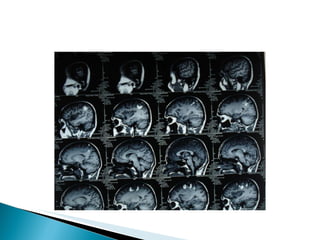

Rpt MRI with MRV and MRA  : -T2 flair showing superior sagital sinus thrombosis. Pt. was started on T.Acitrom 4mg with target INR of 2-3. Pt. was screened for pro coagulant conditions and they are negative(lupus anti coagulant, Protein C & S, anti thrombin III defi. and Sr.Homosysteine).

Combination of non contrast MRI and MRA and MRV : best method for the diagnosis and follow up of CVT . MRI/V  -Early: absence of flow void & isointense on  T1 for occluded vessel;  Hypo intense on T2 Late: hyper intense thrombus on T1 & T2

Rpt MRI withMRV and MRA : -T2 flair showing superior sagital sinus thrombosis. Pt. was started on T.Acitrom 4mg with target INR of 2-3. Pt. was screened for pro coagulant conditions and they are negative(lupus anti coagulant, Protein C & S, anti thrombin III defi. and Sr.Homosysteine).

Combination of noncontrast MRI and MRA and MRV : best method for the diagnosis and follow up of CVT . MRI/V -Early: absence of flow void & isointense on T1 for occluded vessel; Hypo intense on T2 Late: hyper intense thrombus on T1 & T2